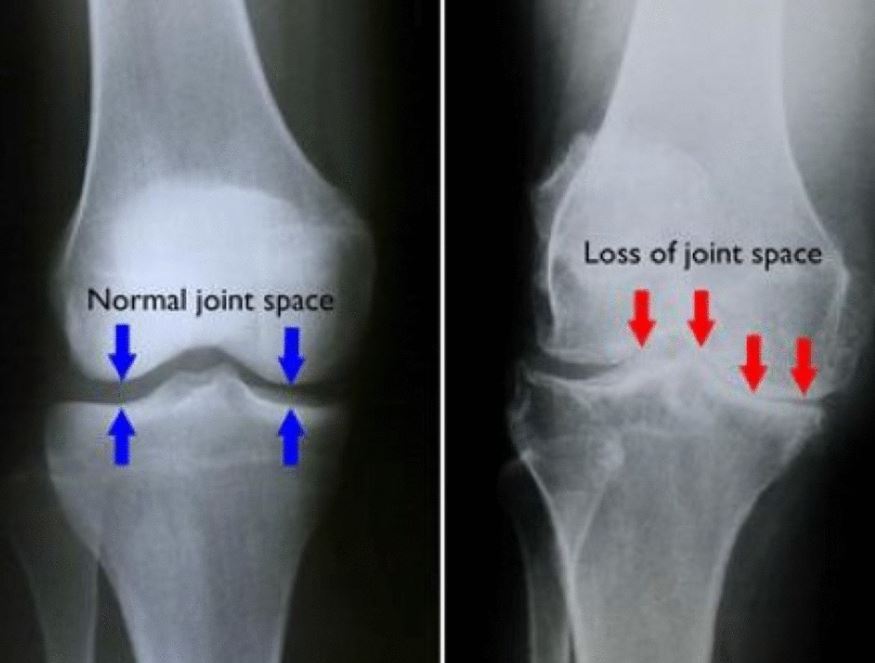

गुडघा प्रत्यारोपण ही शस्त्रक्रियाची प्रक्रिया आहे ज्यामध्ये खराब झालेले गुडघा मेटल किंवा प्लास्टिक इम्प्लांटने गुडघ्याच्या सांध्याद्वारे बदलला जातो. याला (गुडघा आर्थ्रोप्लास्टी) असेही म्हणतात. गुडघा प्रत्यारोपण शस्त्रक्रिया दुखापत किंवा संधिवात वेदना कमी करण्यासाठी आणि कडकपणा कमी करण्यासाठी वापरली जाते. गुडघा प्रत्यारोपण आणि पुनर्प्राप्तीनंतर, आपण दैनंदिन काम करू शकता.

संधिवातावर उपाय

शरीरातील एकापेक्षा जास्त सांध्यांना सूज येणं किंवा तीव्र वेदाना होणं याला 'आर्थरायटीस' किंवा संधिवात म्हणतात. हा प्रामुख्याने वृद्धांना होणारा आजार आहे. वाढत्या वयासोबत हळूहळू वाढत जाणारा आजार मानला जातो. असं असलं तरी लहान मुलं आणि युवकांनाही हा आजार होण्याची नाकारता येत नाही.

लक्षण : सांधेदुखी, सांध्यांमध्ये जाणवणारी ताठरता (stiffness), सूज, सांध्यांजवळचा भाग लाल होणं, चालण्या-फिरण्यात किंवा हालचाल करण्यात येणारा अडथळा etc.